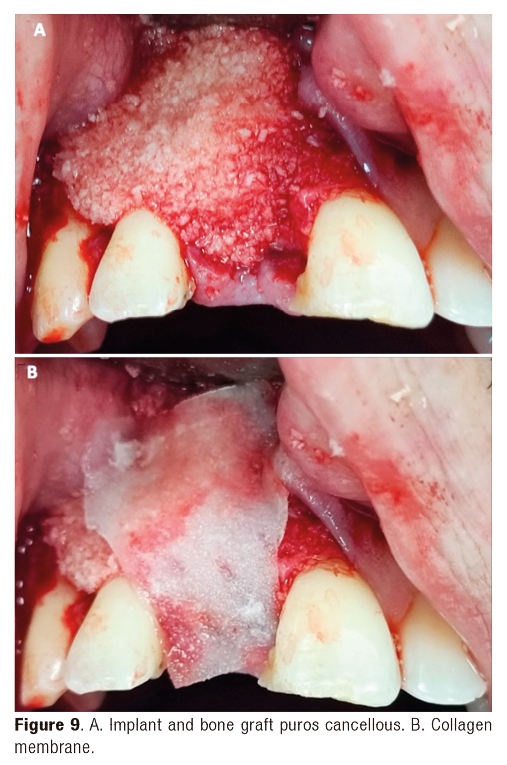

A 36-year-old male patient who required an extraction of the upper right central incisor finding a type II socket with a dehiscence of 50% associated to thick biotype by this reason is chosen an immediate implant placement with bone graft puros cancellous and resorbable membrane adjacent to provisional tooth (Figure 9).